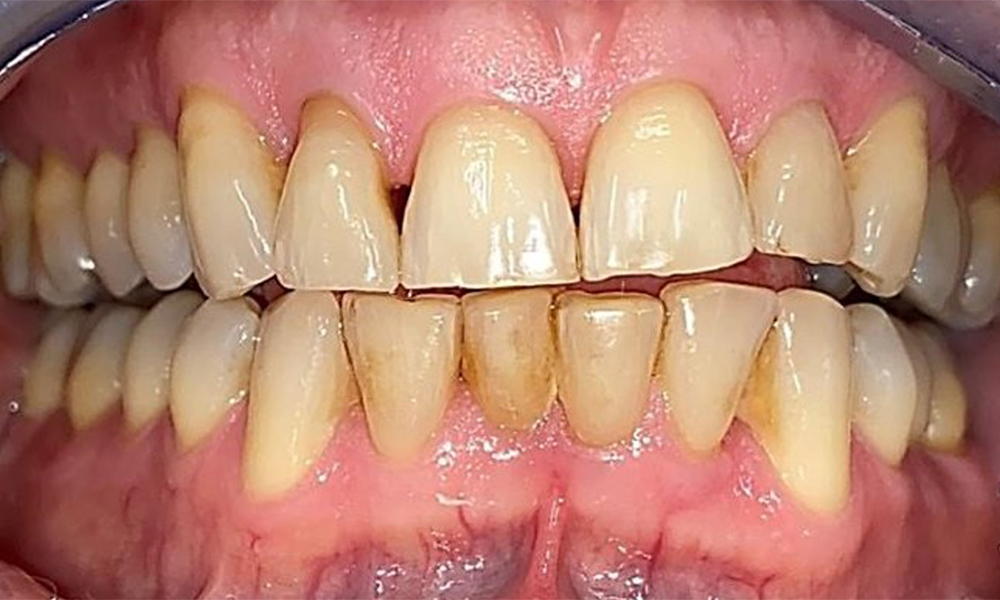

Der Patient hat ein vollbezahntes Gebiss mit 28 Zähnen, an welchen sich im Molaren- und Prämolarenbereich Amalgamfüllungen und Compositefüllungen befinden. An Zahn 14 zeigt sich ein sichtbarer klinischer Randspalt. Zahn 27 hat ein suffizientes Goldinlay. Zudem zeigen sich generalisierte Attritionen und Abrasionen. (Abb. 2, Abb. 3, Abb. 4, Abb. 5, Abb. 6)

Der Patient hat eine Parodontitis Stadium II, Grad B (5). Die klinischen Sondierungstiefen liegen mit 1-3mm im physiologischen Bereich. Lokalisierte Sondierungstiefen finden sich an 17 und 27 jeweils mesiopalatinal mit 5mm. Es liegen generalisierte Rezessionen von 1-3mm vor mit partiellem Verlust der Interdentalpapillen (Abb. 2, Abb. 3, Abb. 4)